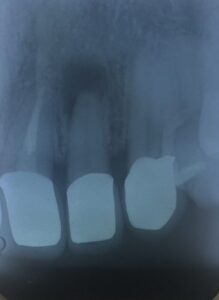

歯根尖端 部分に 肉芽腫様 の 骨吸収像が 観えます。

根管治療が 終わって

2年 経過。

無菌的 根管治療を 行えば

ホラっ!

歯槽骨 回復して きました よっ!